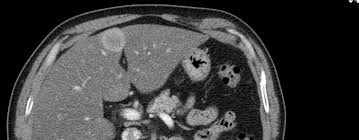

Development Of An Orthotopic Model Of Human Metastatic Prostate Cancer In The Nod Scidg Mouse Mus Musculus Anterior Prostate

Development Of An Orthotopic Model Of Human Metastatic Prostate Cancer In The Nod Scidg Mouse Mus Musculus Anterior Prostate from www.spandidos-publications.com